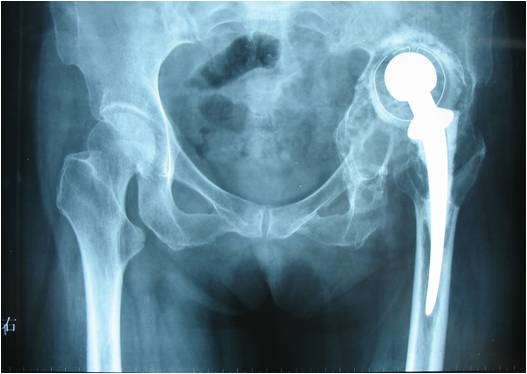

19髋中,18髋的髋臼假体稳定,未发现臼杯在垂直和水平方向大于1mm的移位,也未发现髋臼假体外展角的改变(图1-3)。有1例PaproskyⅢB型患者出现金属网及髋臼杯明显移位等影像学松动表现:术后12月随访时,髋臼上移16.8mm,内移4.7mm;术后28月时,髋臼上移22.7mm,内移5.8mm,髋臼假体外展角较术后减小2.2°(图4-6)。但患者髋关节疼痛不明显,日常生活中能无需手杖独立行走,拒绝再次翻修手术。

图1 全髋关节置换术后无菌松动,髋臼PaproskyⅢA型骨缺损

图2 术后6周,臼底缺损用金属网封闭

图3 术后36月 异体骨整合良好